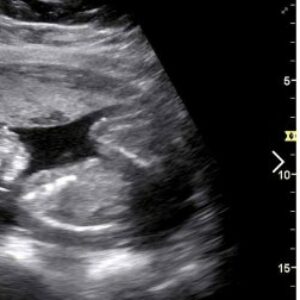

La edad media para tener el primer hijo se retrasa a los 31 años y disminuyen los niños por mujer En una sola década, los nacimientos han caído casi un 30% en España. Ha disminuido el número de hijos por mujer y se ha retrasado la edad de la maternidad hasta el punto de que […]

Ovario poliquístico y embarazo no son incompatibles. El síndrome de ovario poliquístico genera problemas ovulatorios que pueden perjudicar a la fertilidad de la mujer. Tal y como te contamos en este otro artículo sobre el síndrome de ovario poliquístico, esta alteración de la ovulación, por la que se crean pequeños quistes en los ovarios, afecta a alrededor del […]